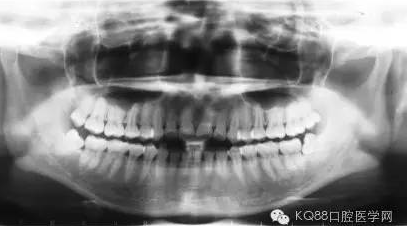

長時間的牙結(jié)石堆積最后會造成牙槽骨吸收和牙周袋形成,牙周袋內(nèi)很容易聚集食物殘渣和細(xì)菌。這樣惡化循環(huán),最后的結(jié)果是牙齒松動、脫落。

牙槽骨一旦吸收很難再生,所以,牙周刮治的目的是為了防止進(jìn)一步的牙槽骨吸收,牙周袋形成以及牙齦出血。更有利于牙齒的穩(wěn)固和健康。

經(jīng)過牙周刮治(包括齦下刮治和跟面平整術(shù))的患者,每3到4個月需要進(jìn)行一次牙周維護(hù),因為他們牙齦下的堆積結(jié)石的幾率比一般人的要高。同時,掌握正確的刷牙方式(每天至少刷兩次),堅持使用牙線,對維護(hù)牙周健康也能起到一定的作用。